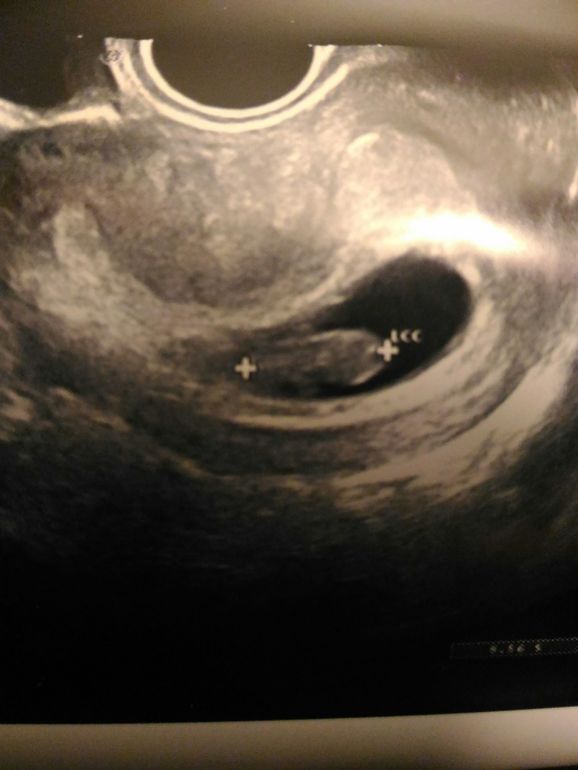

Всё о нашей беременностиБыла сегодня на узи, ну надо уже было посмотреть на нашу крошку.

2 недели не видела с последнего узи и то из-за коричневой мазни. Доктор померила тело малютки - 1.9 мм от макушки до попки, серцебиение как паравоз. Постоянно в движении, что-то там копошился. Короче, похож внешне на мишку.

Доктор также сказала, что все соответствует 8 неделе развития.